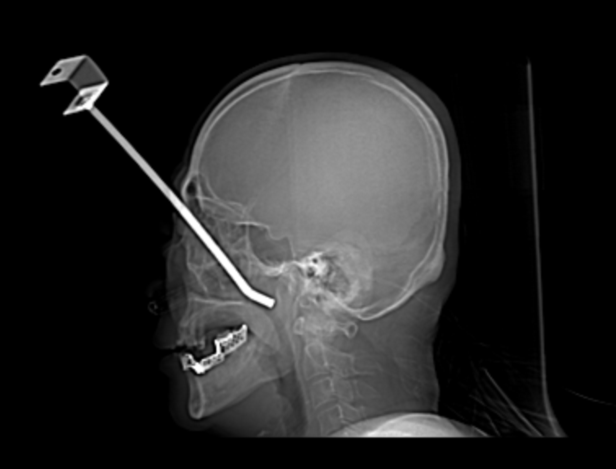

6月10日凌晨,一场与时间赛跑的“光明保卫战”在兰大二院急诊科上演。一名中年男性患者因意外跌倒,被钢管深插入眼部,情况十分危急,入院后,经初步检查显示,钢管位置极深且位置险要,紧邻眼球及颅内重要结构,如不及时精准施救,患者将面临生命危险甚至永久性失明。

危急时刻,医院医务处迅速启动重大创伤应急响应,第一时间组织耳鼻咽喉科、眼科、神经外科、口腔科等多学科专家进行紧急会诊。综合研判后,专家团队一致认为手术风险极高、难度极大。鉴于异物位置深在鼻眶颅底交界区域,最终决定由耳鼻咽喉科主导实施手术。

耳鼻咽喉科主任徐百成立即组织团队,针对术中可能出现的大出血及毗邻结构(鼻窦、上颌骨、颅底、眼眶、眼球及视神经)损伤的巨大风险,制定了精准的手术入路规划和详尽的应急预案。术中,在麻醉科、眼科、重症医学科等多学科团队的严密监护与协作支持下,由耳鼻咽喉科副主任医师刘增平、陈迟主刀,凭借精湛的鼻内镜微创技术和对颅颌面复杂解剖结构的精准把握及沉稳操作,对鼻窦、上颌骨、颅底、眼眶壁及眼球结构进行分层保护,并严格控制出血,有效规避了各类并发症的发生。经过紧张有序的奋战,钢管被完整、安全地取出,手术过程顺利,患者生命得以挽救并最大程度保护了其眼球和视神经功能,术后患者状态平稳,已转入普通外科ICU进行进一步治疗。